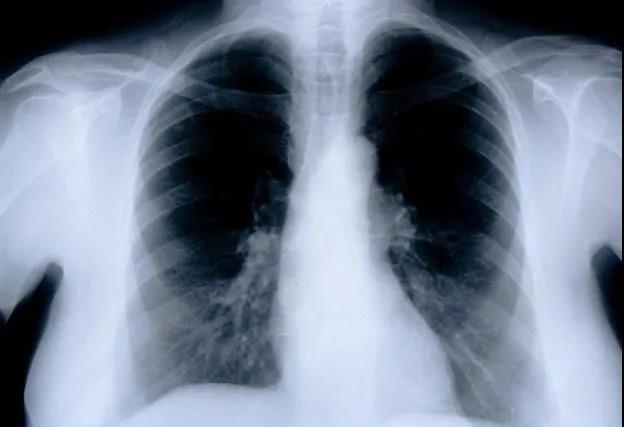

原发性支气管肺癌,简称肺癌,是我国乃至全球发病率和死亡率最高的恶性肿瘤(图1)。流行病学资料显示,截止2018年,全球大约有1810万癌症新发病例和960万癌症死...